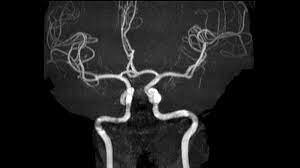

La angiografía digital ha mejorado el estudio y tratamiento de las patologías vasculares. La angiografía digital ha mejorado el estudio y tratamiento de las patologías vasculares.

Permite reconstrucciones tridimensionales. Permite reconstrucciones tridimensionales.